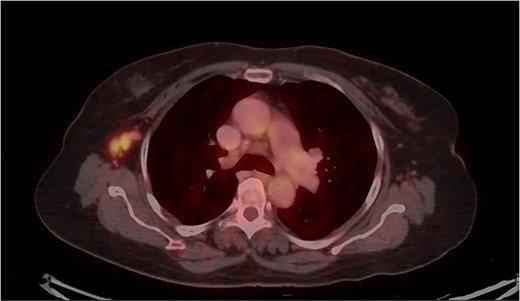

Mammography revealed an asymmetrical density in the upper outer quadrant of the right breast with BIRADS V classification. Ultrasonography identified an irregular hypoechoic lesion measuring 3.8 × 2.5 cm in the right breast. Additionally, multiple enlarged axillary lymph nodes with cortical thickening were seen, the largest measuring 1.02 cm in diameter. A core needle biopsy of the breast lesion demonstrated features of invasive carcinoma, not otherwise specified (NOS), Grade II based on the Nottingham grading system. Immunohistochemistry revealed the tumor to be ER-positive (78%), PR-negative, Her2Neu-negative, and Ki67–21%, confirming it as Luminal A subtype. The excised axillary lymph nodes exhibited caseating granulomatous inflammation, consistent with tuberculosis (Fig. 1). Acid-fast bacilli (AFB) testing further confirmed the diagnosis of TB. Pre-surgical imaging revealed metabolically active areas in the breast lesion and axillary lymph nodes with no evidence of systemic metastases (Figs 2 and 3).

PET-CT axial view of the thorax, indicating a metabolically active lesion in the right breast.

PET-CT axial view of the thorax, indicating a metabolically active lesion in the right axillary region, involving the right axillary lymph nodes.